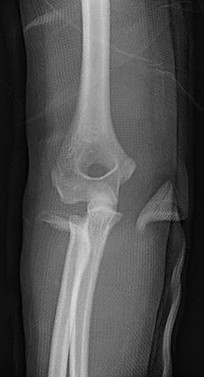

Question 13:

A 6-year-old boy sustains a severe extension-type supracondylar humerus fracture after a fall. Radiographs classify it as a Gartland Type III. The distal fragment is severely displaced posteromedially relative to the proximal shaft. Based on this specific displacement pattern, which of the following nerve structures is at greatest risk of tethering or injury from the proximal fragment?

Correct Answer: Radial nerve

Explanation:

In an extension-type supracondylar humerus fracture, the displacement of the distal fragment dictates the direction of the proximal spike. If the distal fragment is displaced posteromedially, the sharp proximal fragment is thrust anterolaterally, placing the radial nerve at the highest risk of injury. Conversely, if the distal fragment displaces posterolaterally, the proximal spike goes anteromedially, placing the median nerve (and AIN) at greatest risk.